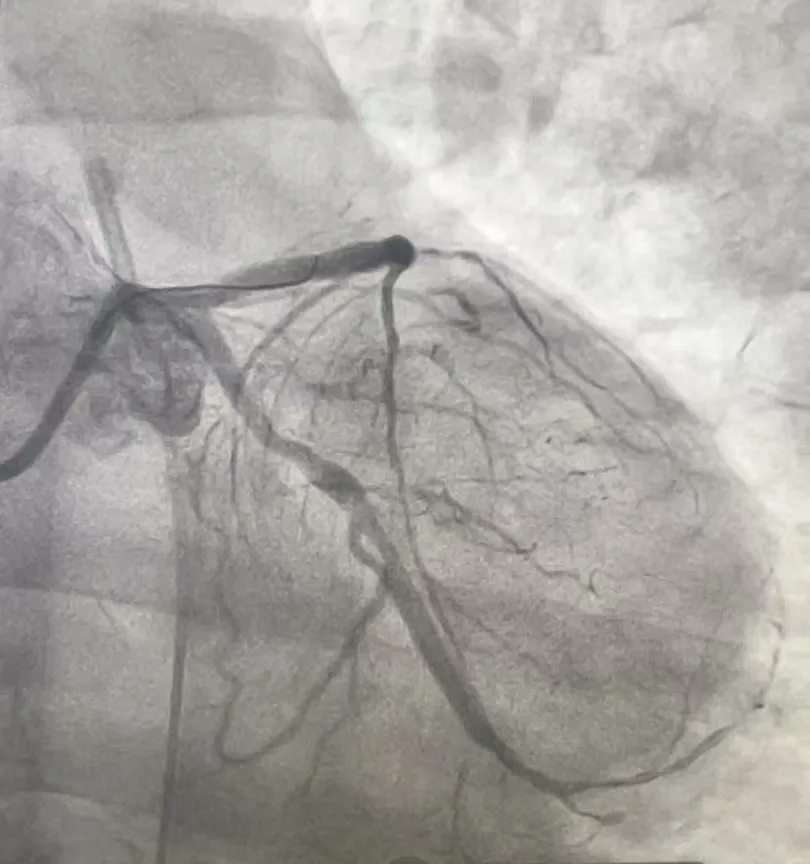

心脏血管造影检查提示,张先生的三支主要血管均存在严重病变。

• 前降支近段完全闭塞,该血管心脏供血的“主干道”之一,负责左心室前壁血液供应,堵塞后极易引发大面积心梗;

• 回旋支中远段完全闭塞,供应心脏侧壁血液,闭塞会加重心肌缺血范围;

• 右冠状动脉中远段弥漫性狭窄,最重处达70%-80%,虽未完全堵死,但狭窄严重,随时可能进展为急性闭塞。

(术前影像)

患者前降支和回旋支同时完全堵塞,相当于心脏的两条重要“高速公路”彻底中断,仅靠右冠残余血流勉强维持,随时可能猝死。